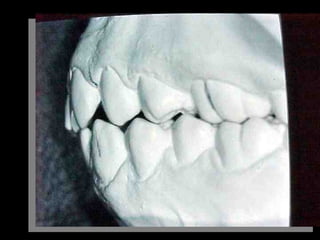

Modelos PreoperatoriosModelos Preoperatorios

Arcada Superior:

Forma oval

Paladar profundo

Totalidad de órganos dentarios a excepción de tercer molar izq.

Restauraciones deficientes

Frente:

Línea media desviada

Mordida cruzada anterior

Arcada Inferior:

Forma ovalada

Colapso posterior

Ligero apiñamiento de anteriores

Rotación de premolares

Modelos vista lateral

prequirúrgica

Clase III molar y caninaClase III molar y canina

Arcada Superior: Forma oval Paladarprofundo Totalidad de órganos dentarios a excepción de tercer molar izq. Restauraciones deficientes Arcada Superior: Forma oval Paladar profundo Totalidad de órganos dentarios a excepción de tercer molar izq. Restauraciones deficientes Frente: Línea media desviada Mordida cruzada anterior Frente: Línea media desviada Mordida cruzada anterior Arcada Inferior: Forma ovalada Colapso posterior Ligero apiñamiento de anteriores Rotación de premolares Arcada Inferior: Forma ovalada Colapso posterior Ligero apiñamiento de anteriores Rotación de premolares

Modelos vista lateral prequirúrgica Modelosvista lateral prequirúrgica 6 6 3 3 Clase III molar y caninaClase III molar y canina